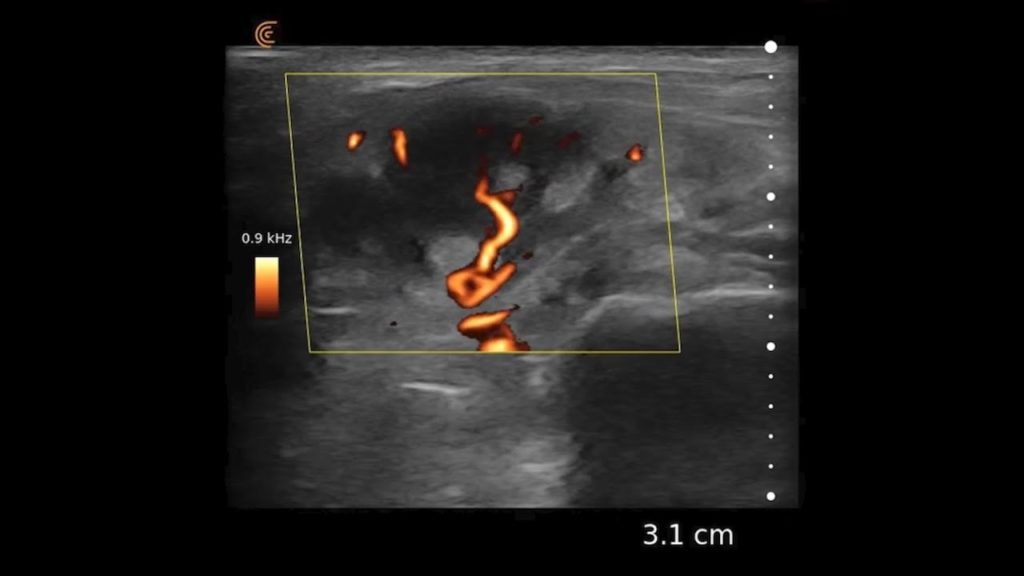

Using the jejunum as an important landmark, the hypoechoic jejunal lymph nodes can be identified. In this video Dr. Edwards explains the ultrasound appearance of normal jejunal nodes.